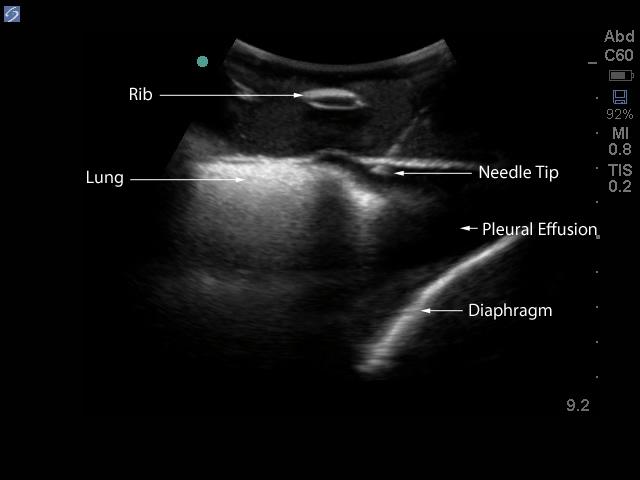

The model is of a supine adult male and extends from the upper buttocks to the lower neck. Positioned in the mid scapulary line, the ultrasound tissue insert contains chest wall superficial tissue, 6th, 7th, 8th, and 9th ribs and intercostal spaces, pleural cavity with lung and atelectatic lung, diaphragm, and superior spleen. The pleural fluid collections allow users to develop and refine their ultrasound guided thoracentesis skills. This model is extremely realistic and is self-healing offering you superb training with a low cost of ownership.

The ultrasound tissue insert offers extremely realistic sonographic imaging characteristics is designed for guiding the placement of needles and small catheters (18-21 gauge and associated catheter kits). Blue Phantom simulated human tissue is very realistic and ultra-durable; excellent for repeated training in skills associated with ultrasound guided thoracentesis procedures. Positive fluid flow offers users feedback when pleural effusions are accurately accessed. The fluid is easily refilled using a quick fill luer lock or can be connected to an I.V. reservoir for continuous fluid delivery. Users can also learn to avoid accessory structures as the spleen, diaphragm and lung.

Ultrasound imaging skills include; using ultrasound system controls, transducer positioning and movement, recognition of thoracic anatomy, lung, diaphragm, anterior spleen and pleural effusions, using ultrasound to target the appropriate fluid pockets for needle guidance, and performing an ultrasound guided thoracentesis procedure. Our self-healing tissue will allow you to repeatedly perform ultrasound guided thoracentesis procedures without giving second thought to wearing out the tissue or calculating the cost per cannulation. You can expect unmatched durability from our tissue. This ultrasound training mannequin is constructed using Blue Phantom’s patented ultra-durable tissue and is extremely realistic in ultrasound imaging characteristics and feels like real human tissue. Our self-healing tissue will withstand tremendous use and will save you money by dramatically reducing the necessity for purchasing replacement parts. Constructed using Blue Phantom simulated tissue which match the acoustic characteristics of real human tissue so when you use your ultrasound system on our training models, you experience the same quality you expect from imaging patients in a clinical environment.

Blue Phantom's mid-scapular thoracentesis ultrasound training model is specifically designed for ultrasound guided thoracentesis procedures. This ultrasound training phantom aids users in developing and practicing the skills associated with a mid scapulary approach to ultrasound guided thoracentesis procedures. This model is excellent for assisting clinicians in gaining proficiency in using ultrasound to identify and guide needle and small gauge catheter insertions in a patient with pleural effusions for diagnostic and/or therapeutic purposes.The model is of a supine adult male and extends from the upper buttocks to the lower neck. Positioned in the mid scapulary line, the ultrasound tissue insert contains chest wall superficial tissue, 6th, 7th, 8th, and 9th ribs and intercostal spaces, pleural cavity with lung and atelectatic lung, diaphragm, and superior spleen. The pleural fluid collections allow users to develop and refine their ultrasound guided thoracentesis skills. This model is extremely realistic and is self-healing offering you superb training with a low cost of ownership.

The ultrasound tissue insert offers extremely realistic sonographic imaging characteristics is designed for guiding the placement of needles and small catheters (18-21 gauge and associated catheter kits). Blue Phantom simulated human tissue is very realistic and ultra-durable; excellent for repeated training in skills associated with ultrasound guided thoracentesis procedures. Positive fluid flow offers users feedback when pleural effusions are accurately accessed. The fluid is easily refilled using a quick fill luer lock or can be connected to an I.V. reservoir for continuous fluid delivery. Users can also learn to avoid accessory structures as the spleen, diaphragm and lung.

Ultrasound imaging skills include; using ultrasound system controls, transducer positioning and movement, recognition of thoracic anatomy, lung, diaphragm, anterior spleen and pleural effusions, using ultrasound to target the appropriate fluid pockets for needle guidance, and performing an ultrasound guided thoracentesis procedure. Our self-healing tissue will allow you to repeatedly perform ultrasound guided thoracentesis procedures without giving second thought to wearing out the tissue or calculating the cost per cannulation. You can expect unmatched durability from our tissue. This ultrasound training mannequin is constructed using Blue Phantom’s patented ultra-durable tissue and is extremely realistic in ultrasound imaging characteristics and feels like real human tissue. Our self-healing tissue will withstand tremendous use and will save you money by dramatically reducing the necessity for purchasing replacement parts. Constructed using Blue Phantom simulated tissue which match the acoustic characteristics of real human tissue so when you use your ultrasound system on our training models, you experience the same quality you expect from imaging patients in a clinical environment.

- Ultrasound tissue module contains the chest wall superficial tissue, 6th, 7th, 8th, and 9th ribs and intercostal spaces, pleural cavity with lung and atelectatic lung, diaphragm, and superior spleen.

- Superb ultrasound imaging characteristics: extremely realistic in ultrasound imaging characteristics and feels like real human tissue

- Ultrasound tissues match the acoustic characteristics of real human tissue so when you use your ultrasound system on our training models, you experience the same quality you expect from imaging patients in a clinical environment